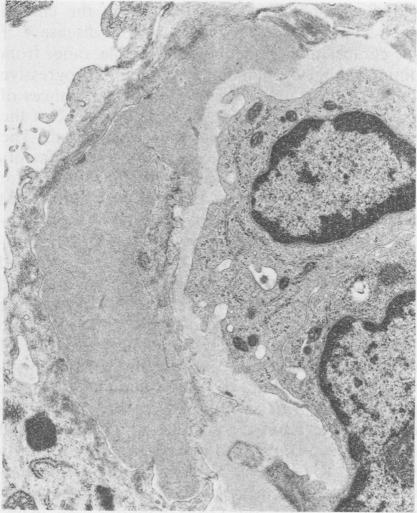

Six patients with coexistent antiglomerular basement membrane disease and granular immunoreactants in the glomerular basement membrane and mesangium are discussed. These six patients represent 35% of all patients with antiglomerular basement membrane nephritis examined over 10 years. All patients presented with acute, oliguric renal failure, and rapid deterioration in renal function. In all patients the pathogenetic role of the antiglomerular basement membrane antibody was confirmed by the demonstration of linear deposits of IgG along the glomerular basement membrane and antiglomerular basement membrane antibody activity in the serum or renal eluates, or both. Evidence for the existence of concurrent immune aggregates was obtained by immunofluorescence studies and electron microscopy. Radioimmunoassays, which were performed in two patients to detect circulating immune complexes, however, yielded negative results. The possible mechanisms concerned in the evolution of this condition and their potential implications are reviewed.

本文讨论了6例同时患有抗肾小球基底膜病且肾小球基底膜和系膜中有颗粒状免疫反应物的患者。这6例患者占10年来所有接受检查的抗肾小球基底膜肾炎患者的35%。所有患者均表现为急性少尿性肾衰竭,肾功能迅速恶化。在所有患者中,通过沿肾小球基底膜的IgG线性沉积以及血清或肾洗脱液中抗肾小球基底膜抗体活性(或两者兼有)的证实,确定了抗肾小球基底膜抗体的致病作用。通过免疫荧光研究和电子显微镜获得了同时存在免疫复合物的证据。然而,对两名患者进行的检测循环免疫复合物的放射免疫分析结果为阴性。本文回顾了该疾病演变过程中可能涉及的机制及其潜在影响。